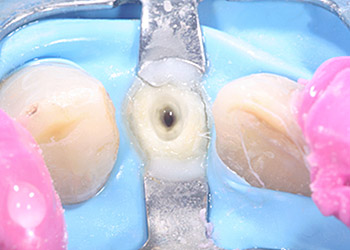

Häufig findet also der Kofferdam seine Anwendung in der Zahnerhaltung, bei Composite-Restaurationen, endodontischen Behandlungen oder Präparationen mit späteren adhäsiven Befestigungen. Denn gerade bei aufwendigen Wurzelkanalbehandlungen, wo der Zahn desinfiziert und von innen gereinigt wird, sollte es vermieden werden erneut Bakterien, z.B. aus dem Speichel in das Wurzelkanalsystem zu transportieren.